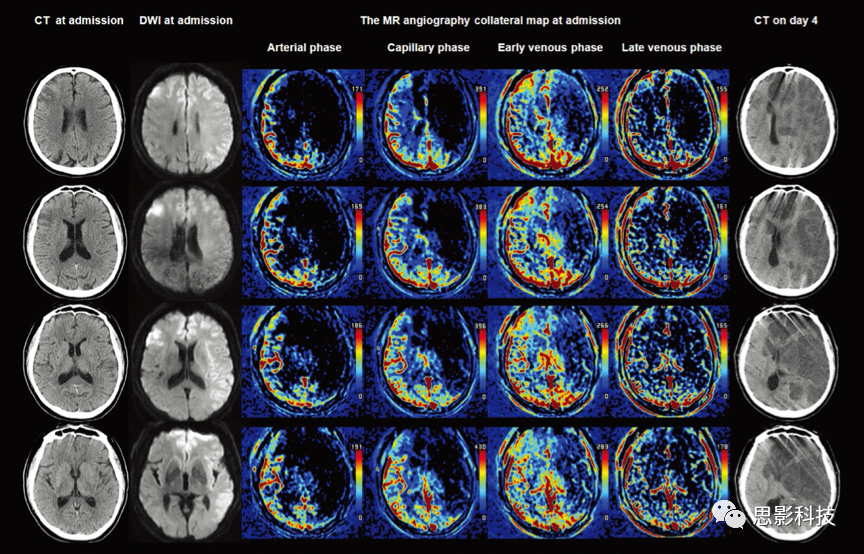

圖注:在左側(cè)小腦中動(dòng)脈梗阻70%以上的74歲男性影像結(jié)果。改良的Rankin量表(mRS)得分為0,美國(guó)國(guó)立衛(wèi)生研究院卒中量表(NIHSS)得分為9。從左往右依次是癥狀發(fā)作6小時(shí)后(入院時(shí))的CT圖像、DWI、多相MRA側(cè)支循環(huán)圖和癥狀發(fā)作后7天的CT圖像。

入院時(shí)CT圖像顯示左中腦動(dòng)脈區(qū)域M2區(qū)域呈現(xiàn)低密度,Alberta卒中項(xiàng)目早期CT評(píng)分為8。入院時(shí)擴(kuò)散加權(quán)圖像的梗死體積為20 mL,多項(xiàng)MR血管側(cè)支循環(huán)造影顯示任何階段左腦半球無(wú)顯著灌注延遲(MR急性缺血性中風(fēng)輔助分?jǐn)?shù)為5:優(yōu)秀)?;颊呓邮芰吮J刂委煵⒖祻?fù),90天mRS得分為0。

圖注:改良的Rankin量表(mRS)得分為0,美國(guó)國(guó)立衛(wèi)生研究院卒中量表(NIHSS)得分為21的64歲男性的影像結(jié)果。從左往右依次是癥狀發(fā)作6小時(shí)后(入院時(shí))的CT圖像、DWI、多相MRA側(cè)支循環(huán)圖和癥狀發(fā)作后第4天的CT圖像。

入院時(shí)CT圖像顯示左腦皮層(Alberta卒中項(xiàng)目早期CT評(píng)分為9)的低密度,以及右前額葉的梗死。入院時(shí)DWI揭示了左中腦和兩側(cè)前腦動(dòng)脈的梗死、右前額葉梗死。多項(xiàng)MR血管側(cè)支循環(huán)造影顯示,側(cè)支助灌注延遲涉及一半以上的左中腦動(dòng)脈區(qū)域,并持續(xù)到晚期靜脈相(MR急性缺血性中風(fēng)輔助分?jǐn)?shù)0:非常差的低壓灌注)?;颊呓邮芰藙?dòng)脈內(nèi)血栓切除術(shù),阻塞的動(dòng)脈在癥狀發(fā)病后3小時(shí)內(nèi)完全重新治療。但最終死于惡性梗死。